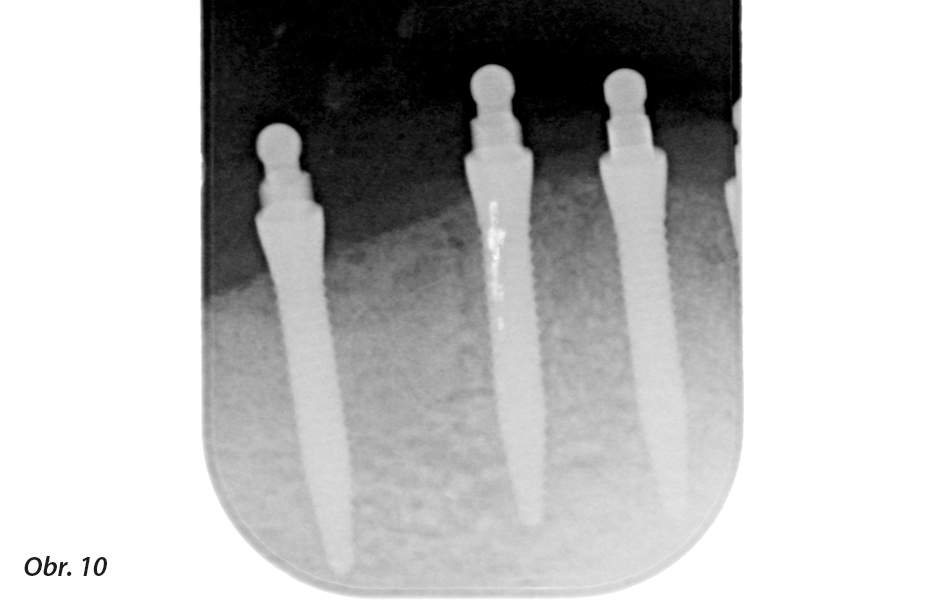

Následné zavedení implantátů (Classic O-Ball, Condent) proběhlo vzhledem k širšímu průměru implantátů v krčkové oblasti již bez nasazené šablony. Pomocí přenosového klíče byly následně jednotlivé implantáty umístěny a částečně zašroubovány (obr. 6). Dále proběhlo zašroubování implantátů pomocí křidélkového nástrčného klíče (obr. 7) a nakonec i jejich dotažení ráčnou (obr. 8). Maximální točivý moment 45 Ncm nebyl přitom překročen, aby nedošlo k případnému poškození periimplantární kosti. Následně proběhla klinická a rentgenová kontrola (obr. 9, 10).

Kontrolní rentgenový snímek zavedených implantátů